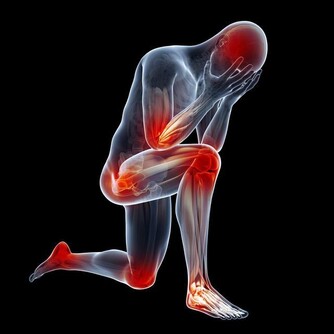

Mary最近開始,走久了就覺得關節有點沒力,應該要好好保養才是啊!

膝關節保養過猶不及,運動過度容易加速磨損,運動不足又容易使關節僵硬,但適度運動的確可以延長膝關節的使用時間!

運動時,以關節不痛為原則,若感到不適應立即停止,並向專業人員諮詢。